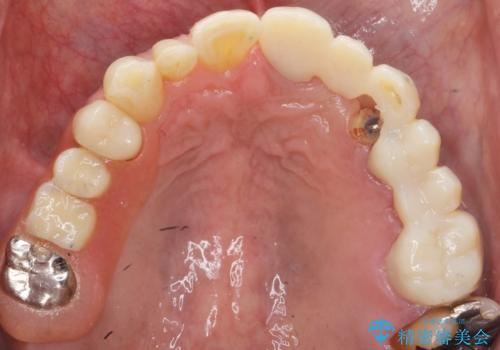

左上2欠損部の軟組織のボリュームが少なくポンティック部に食渣がたまりやすい歯肉形態であったため、歯槽堤増大術も提案しましたがご希望されませんでした。

ご希望により最終補綴前にホームホワイトニングを行っております。

最終補綴前に右上321の結合組織移植術(CTG)を希望されたため、大元院長に行って頂きました。